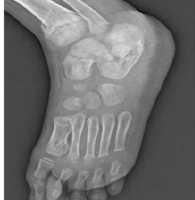

A 16-year-old girl student, from the Benin Republic, presented in our department with increasing right ankle pain. These pains began suddenly 4 months ago, without any trauma, and were maximal on walking. There was no fever, swelling, or weight loss. Personal and family histories were non-contributory. Physical examination was normal. Right ankle radiographs and computed tomography (CT) scan (Fig. 1 and 2) showed an osteolysis lesion type I a of Lodwick et al. [5], of the body and neck of the talus, with heterogeneous cortical effraction on the subtalar articulation.